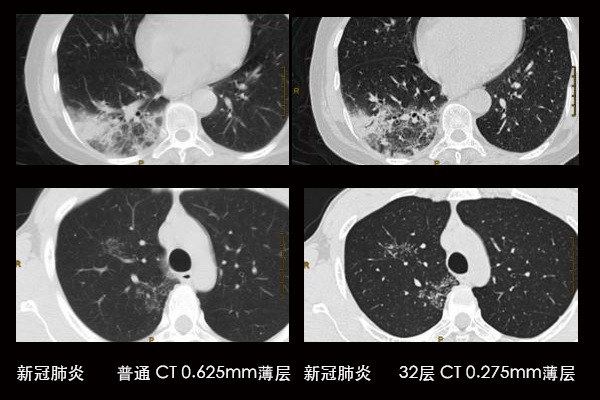

世界独有专利 “0.275”薄层扫描技术。 目前世界上最薄的扫描层厚只能做到0.5mm,而层厚越薄,对比分辨率越高,看到的细节也越清晰,该32层CT做到了目前极致的 0.275mm 超薄层厚扫描

扫描层厚最薄

肺小结节分析:可以分辨最小 2mm 以下早期肺小结节,可以对早发的肺肿瘤及时发现,提高治愈率

临床上最常见病历:对新冠肺炎,炎症侵润节段高清显示,肺炎发展程度分级,细微病灶显示